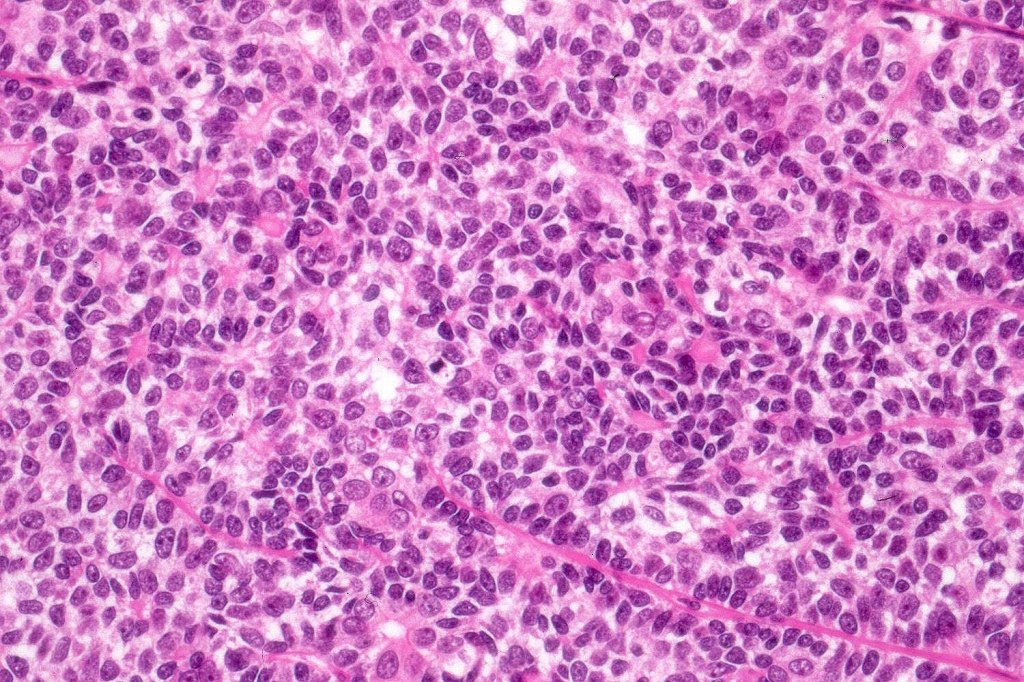

Histological features

•Pre-existent spiradenoma

•Malignant component shows loss of dual cell population, increased mitotic activity, atypical mitoses & necrosis

•Diagnosis depends on H/E rather than IHC